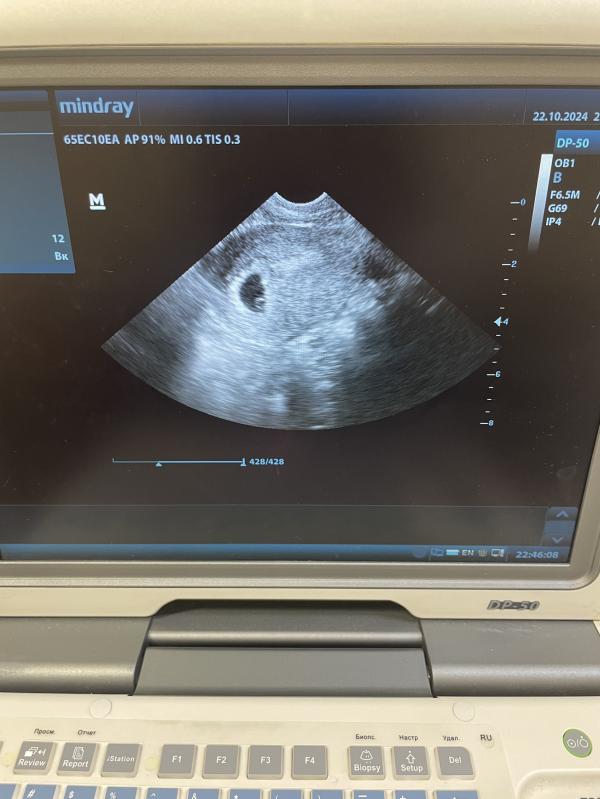

УЗИ на этой неделе: все ли хорошо? Когда следующий визит и фото на память

Заодно врач посмотрела на УЗИ, и конечно же захотелось это запечатлеть на память и поделиться ☀️🤗

7 ноября следующий визит на УЗИ 😌